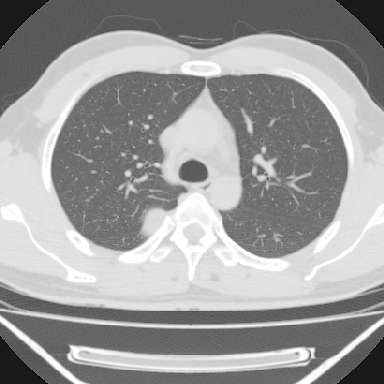

m 30 右胸痛10年

右上后纵隔脊柱旁类圆形肿块,边界光整,与胸腔呈钝角,首先考虑来源于肺外,神经源性肿瘤(神经鞘瘤可能大,神经鞘瘤)

右上后纵隔旁软组织肿块影,与肺界面光滑,与胸壁呈钝角相交,提示肺外病变。位于肋骨下缘,边缘清楚,呈三角样指向与右侧椎间孔,但并示进入椎间孔;与对侧神经根对比,属同一走行方向。

考虑后纵膈良性肿瘤,神经源性肿瘤可能大。

鉴别:胸膜来源肿瘤。影像表现虽有肺外征象,但无胸水等相应佐证;再者,病史前10年,超长,与胸膜肿瘤不太吻合。

建议:再次查体,问清疼痛部位,如为1~2个肋间痛则神经源性肿瘤可能大,如疼痛较弥散,不按肋间分布,则可能为后纵膈其它来源肿瘤。

右上后纵隔脊柱旁类圆形肿块,边界光整,与胸腔呈钝角,首先考虑来源于纵膈,神经源性肿瘤可能大。

右上后纵隔脊柱旁见长椭圆形肿块,边界光整,与胸壁呈钝角。周围骨质未见异常。

考虑、1、后纵隔神经源性肿瘤;

2、不除外单发胸膜间皮瘤。